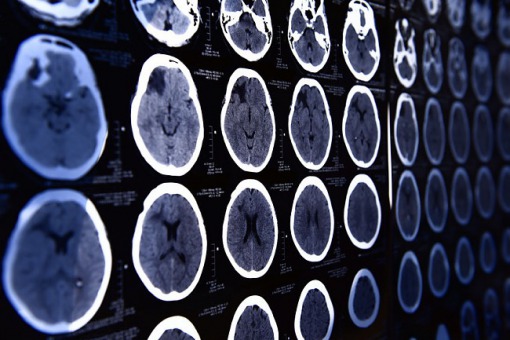

Ogółem 69 oponiaków w grupie eksponowanej (w czasie 289 544 osobolat obserwacji) i 20 oponiaków w grupie kontrolnej (podczas 439 949 osobolat obserwacji) leczono operacyjnie lub radioterapią. Częstość występowania oponiaka w obu grupach wynosiła odpowiednio 23,8 i 4,5 na 100 000 osobolat (ryzyko względne 5,2, 95% przedział ufności 3,2 do 8,6; skorygowany współczynnik ryzyka 6,6, 95% przedział ufności 4,0 do 11,1). Skorygowany współczynnik ryzyka dla skumulowanej dawki octanu cyproteronu większej niż 60 g wyniósł 21,7 (10,8 do 43,5). Po rocznym odstawieniu cyproteronu octanu ryzyko wystąpienia oponiaka w grupie eksponowanej było 1,8-krotnie (1,0 do 3,2) większe niż w grupie kontrolnej. W analizie uzupełniającej obserwowano 463 kobiety z oponiakiem wśród 123 997 kobiet stosujących już octan cyproteronu w 2006 r. (ryzyko 383 na 100 000 osobolat w grupie o największej ekspozycji pod względem dawki skumulowanej). Oponiaki zlokalizowane w przedniej i środkowej podstawie czaszki, obejmujące obszar oczodołowo-klinowy, wydają się być specyficzne dla octanu cyproteronu. Dodatkowa analiza uczestników transpłciowych wykazała wysokie ryzyko wystąpienia oponiaka (3 na 14460 osobolat; 20,7 na 100 000 osobolat).

Zaobserwowano silną zależność dawka-efekt pomiędzy stosowaniem octanu cyproteronu a ryzykiem wystąpienia oponiaków wewnątrzczaszkowych. Po zaprzestaniu leczenia obserwowano zauważalne zmniejszenie ryzyka.